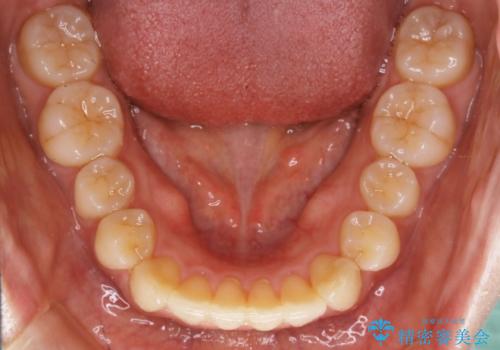

- 前歯のガタつきと噛み合わせの治療を主訴にご来院されました。

健康な歯を抜きたくないというご要望もあり、マウスピースで歯列全体を後方へ移動させてスペースを作り症状の改善を行いました。

マウスピースとマイクロインプラントを組み合わせることで、抜歯をしなくても歯並びを治すためのスペースを作ることができます。奥歯から順に移動させていくので前歯に変化が出るまでには時間がかかりますが、その分健康な歯を抜歯することなく理想的な歯並びを手に入れることができます。